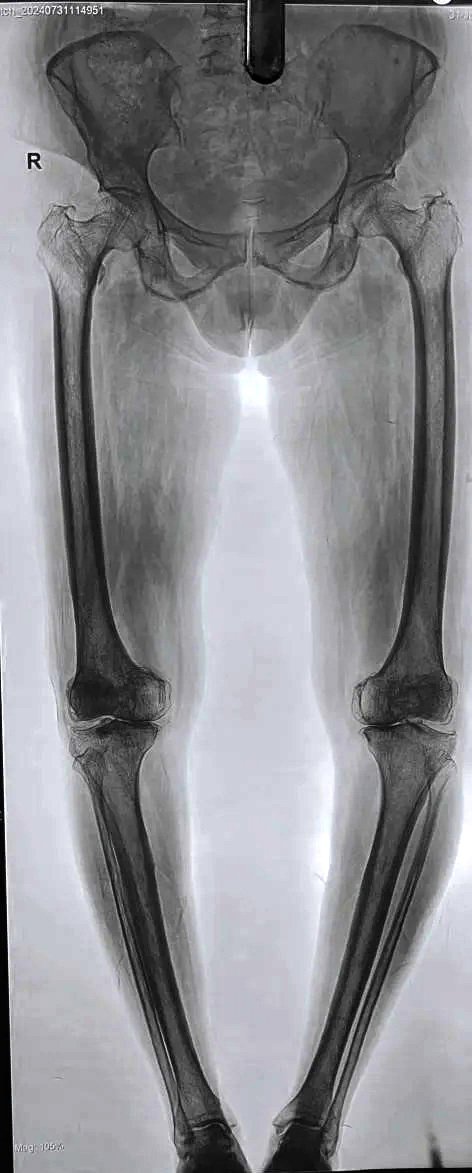

Pre-Op Scanogram

OA Knee with Fixed Flexion Deformity & Non correctable Varus